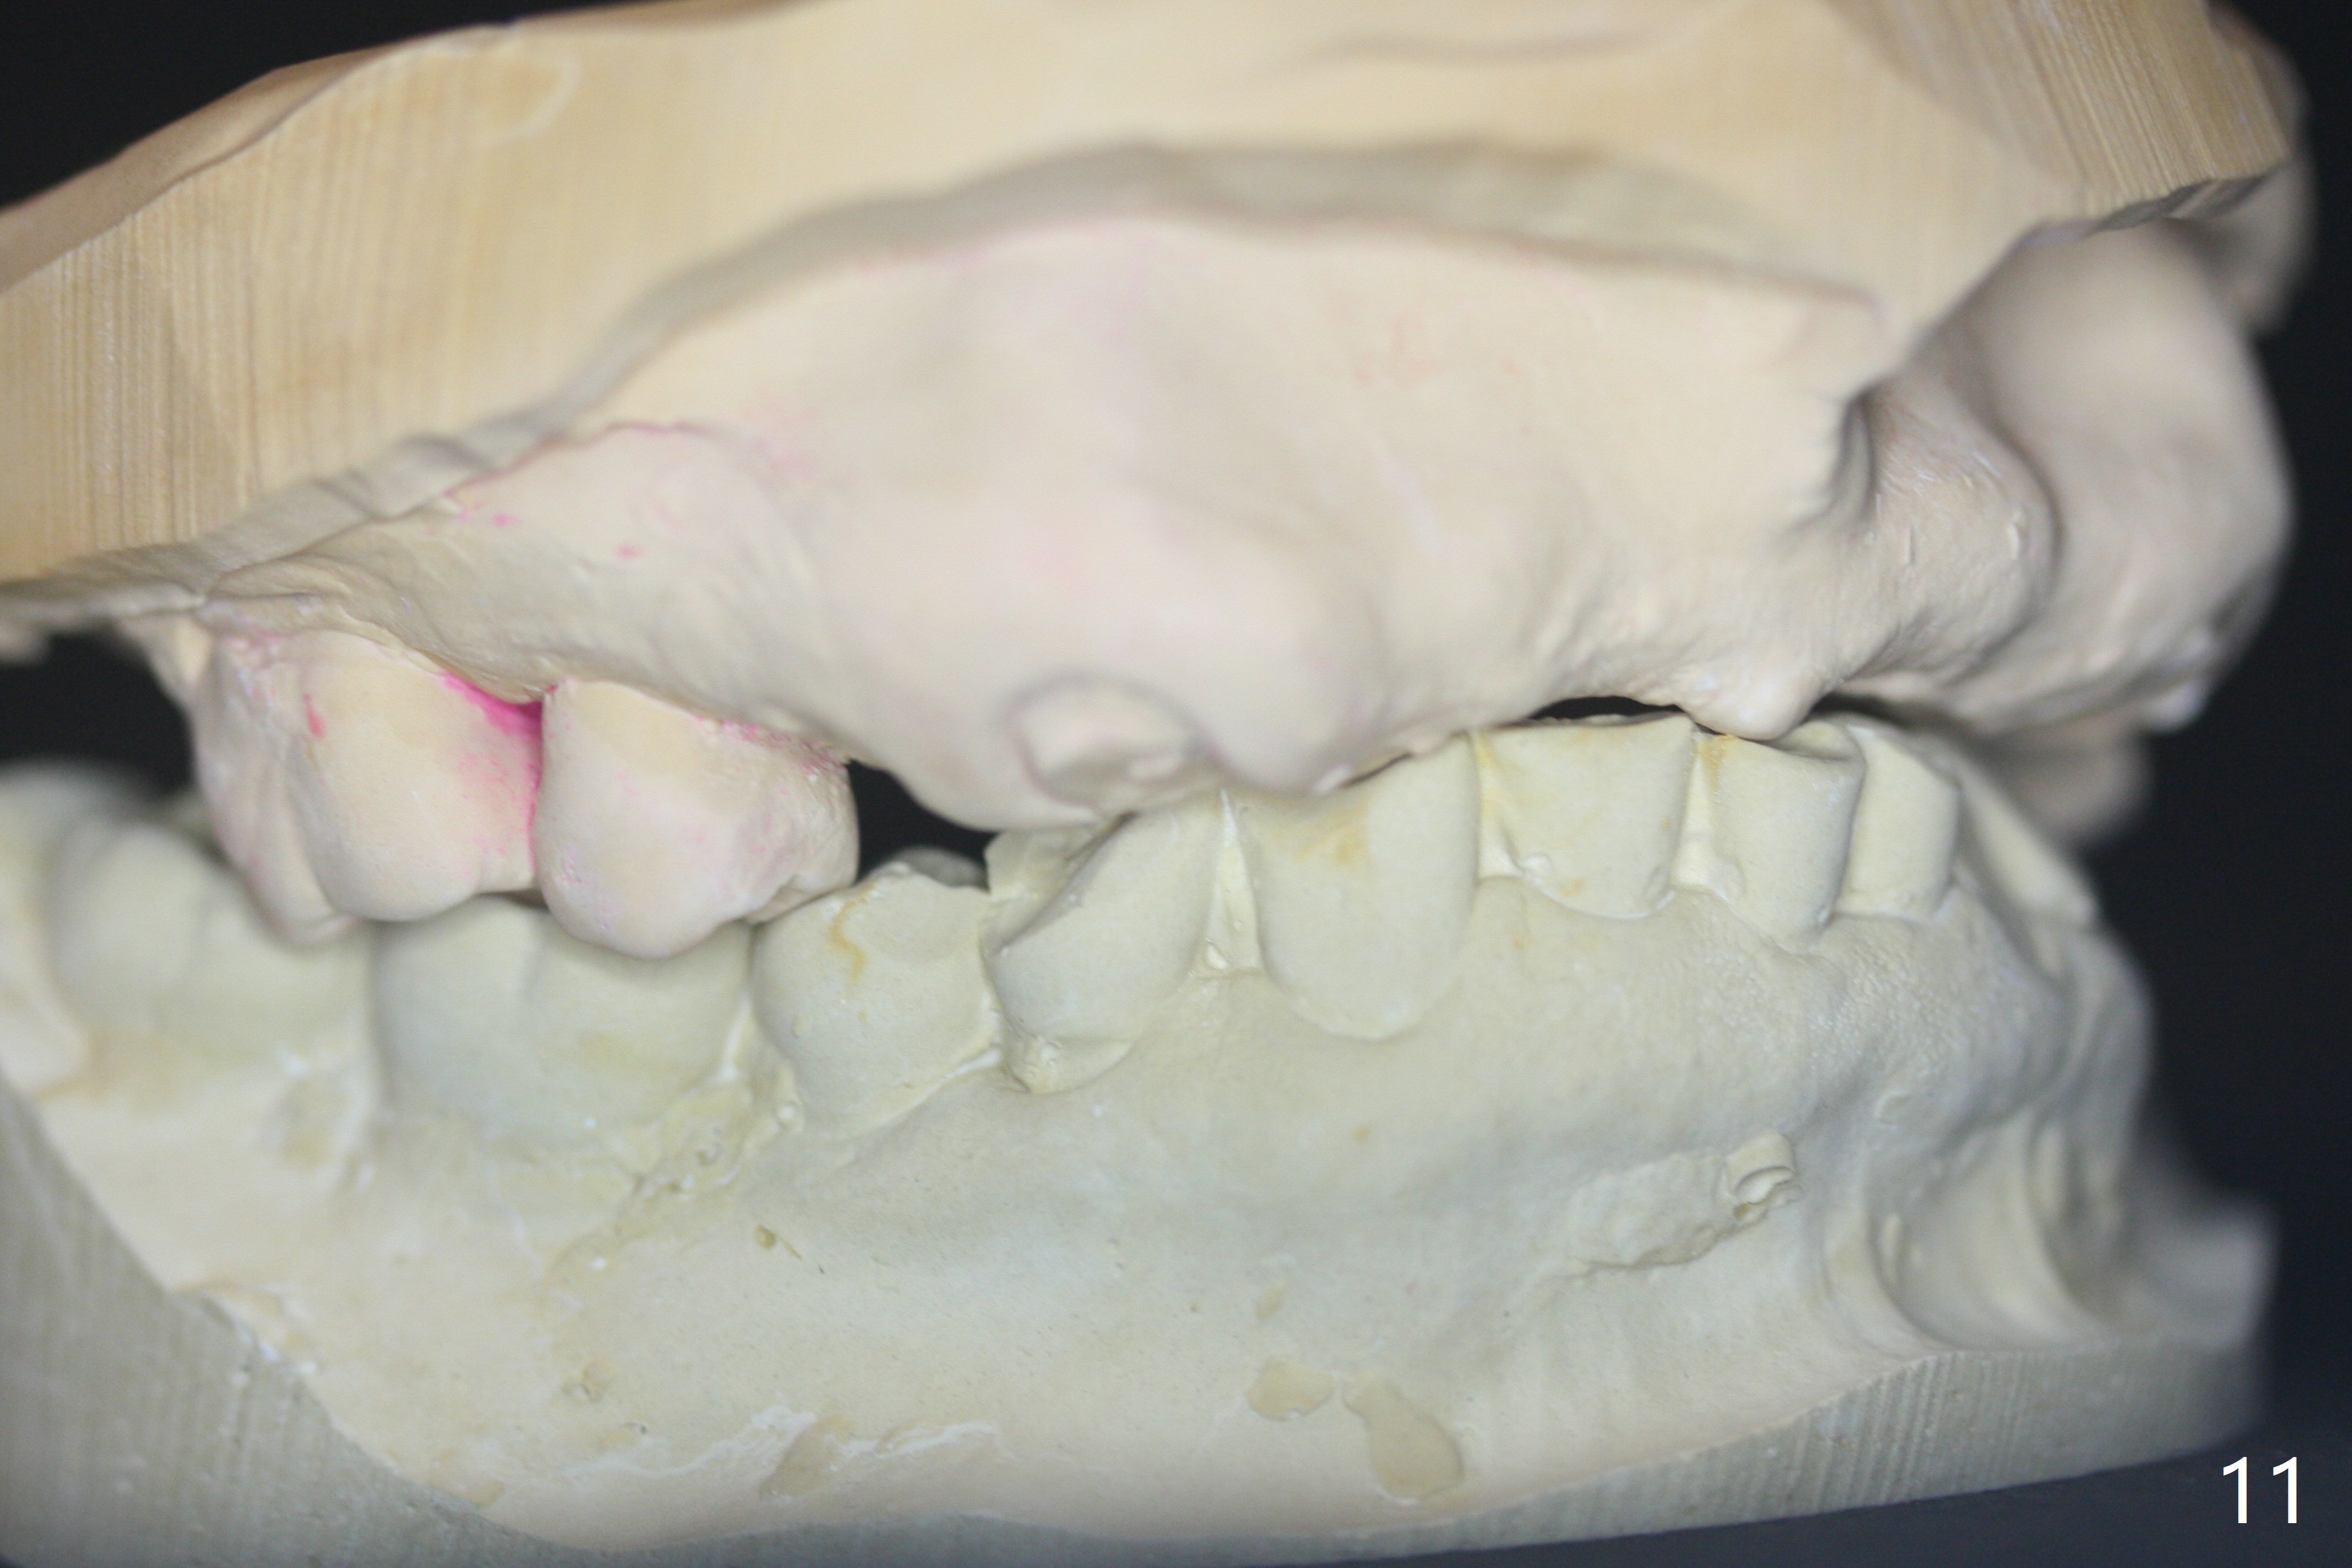

It is smooth and quick to finish osteotomy with guide at #6,7,10-12, but when 3 mm 1-piece implants are placed free hand at #7 and 10 (Fig.1,2), the gingival parts of the abutments contact the incisal edges of the lower incisors (anterior deep bite) in spite of effort to change the trajectory by repeated back and forth placement after use of Lindamann bur buccally. Following an immediate provisional (Fig.3,4), the occlusal surface of the posterior teeth are raised to eliminate anterior restoration interference. Immediate postop CBCT shows that the implants at #7 and 10 could be placed more buccally (Fig.6,7, as compared to the normal position at #6,11,12 (Fig.5,8,9)). Fig.10 was taken 2 days preop, while Fig.11-13 postop. Can we change 1-piece implants (3mm) at #7 and 10 to 2-piece one (3.5) and use angled or cementation abutments for easy restoration (Fig.14-16)?